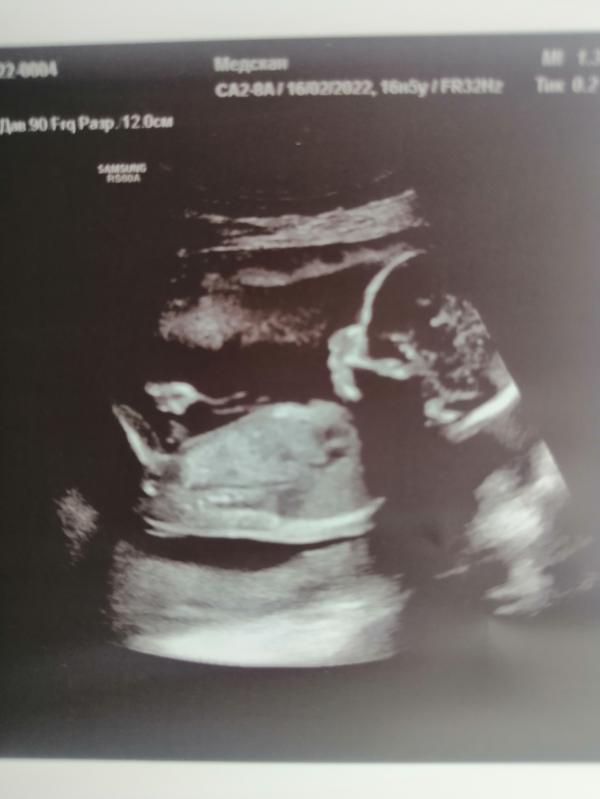

Кто там умеет по бугорку пол определять?!)

Записка с полом в конвертике) решила здесь спросить мнение)

Мальчик, я яички вижу, как у своего. Похоже очень. 😁Напишите хоть потом, угадали мы и или нет

Мне кажется тоже, что девочка, у дочки примерно так же было) у мальчиков на вашем сроке прям торчит все

У меня мальчик и точь в точь такой же профиль на этом сроке 😁 предположу, что мальчик

У нас гендер будет) конверт уже отдали друзьям) решила здесь спросить мнения)